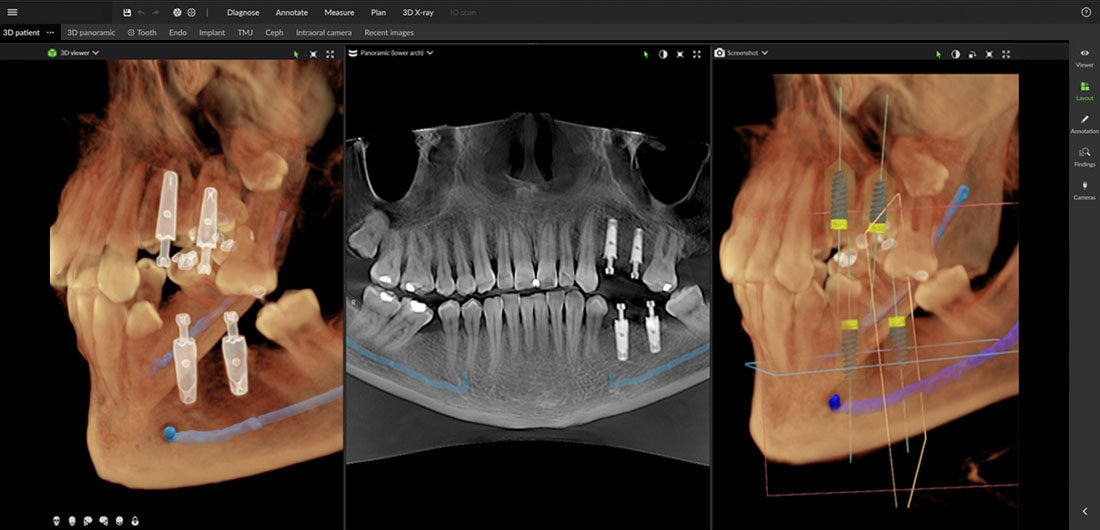

Implantátum behelyezés

Legyen szó szóló implantátum behelyezéséről vagy All-on-4 technológia alkalmazásáról, a DEXIS OP 3D LX lehetővé teszi a többdimenziós képalkotást a műtét előtti diagnózis felállításához valamint a lehető legprecízebb implantátumbeültetés támogatásához.

Fogpótlások

A rendszer támogatja a tökéletes vizualizácót azáltal, hogy lehetővé teszik a szakorvos számára a 3D adatok és az intraorális szkennelés adatainak egyesítését a páciens anatómiájának teljes megjelenítéséhez.

A 3D technológiára épülő multimodalitású képalkotó platform lehetőségei a fogászati felvételi igények teljes spektrumát lefedik, az endodontiától a legösszetettebb implantációs esetekig.